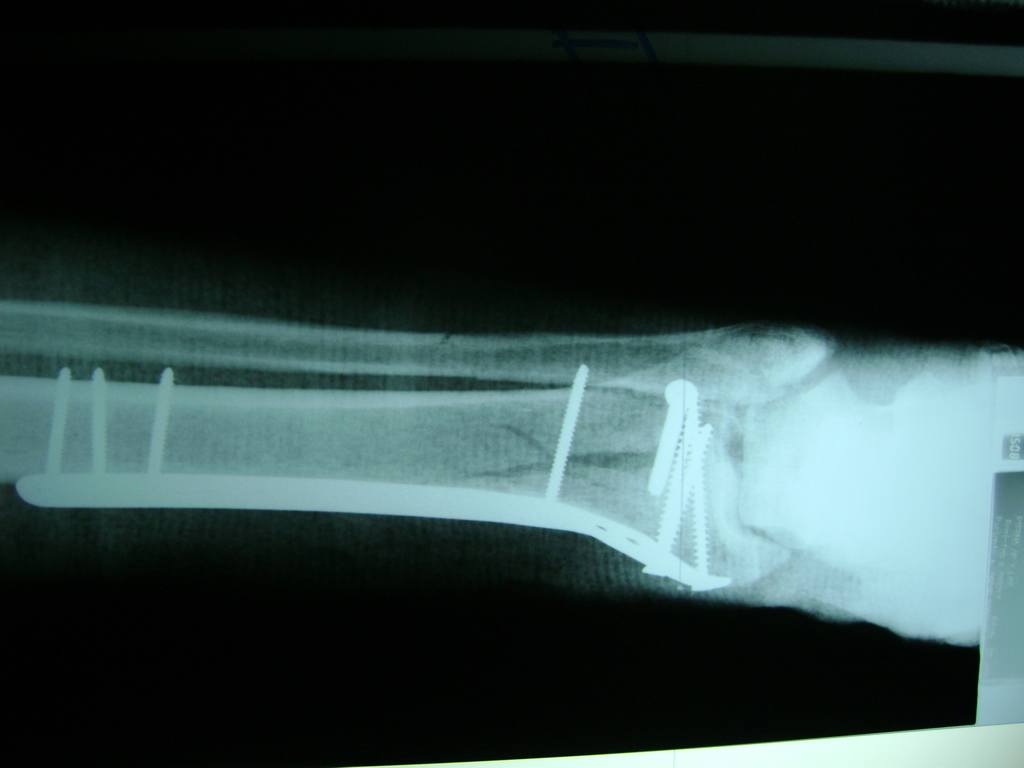

Aunque cada uno de estos huesos puede fracturarse por separado, normalmente la rotura es una lesión que se produce de forma conjunta

La mayor parte de las roturas implican a la parte proximal del hueso (parte del hueso próximo a la rodilla) o a la parte distal (parte del hueso cerca del tobillo).

Debido a la fina cobertura de piel que recubre la tibia y el peroné, las fracturas generalmente son abiertas, es decir, el hueso roto rasga la piel, atravesándola. Las fracturas de tibia y peroné generalmente se producen por un fuerte impacto o torsión.